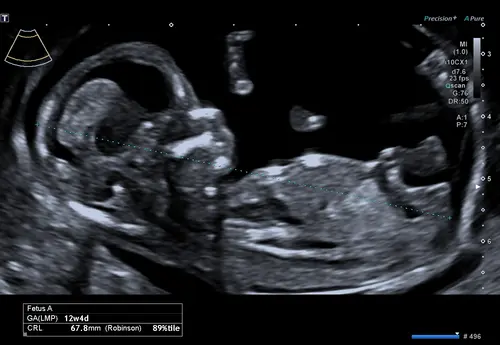

Is hier iets op te zien? 13.0 precies.

Iemand een idee? In de vorige topic 2x meisje 1x een jongentje werd er gezegd maar vandaag een nieuwe echo gehad bij de 13.4 weken vandaar nogmaals de vraag 😊